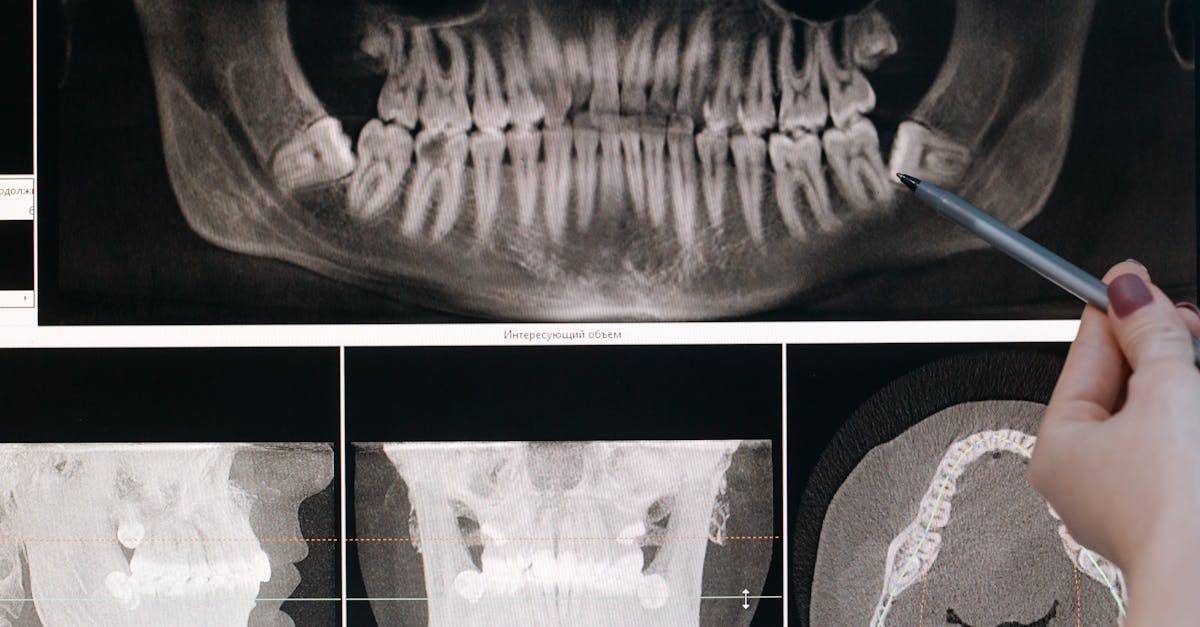

4. Temporomandibular Joint Disorder - The Jaw Pain Dilemma

Temporomandibular Joint Disorder (TMD) encompasses a group of conditions affecting the temporomandibular joints, jaw muscles, and associated structures, with chronic pain being a predominant feature in many cases. The Diagnostic Criteria for Temporomandibular Disorders (DC/TMD) protocol, developed through extensive international collaboration, provides a standardized approach to TMD diagnosis using a dual-axis system that addresses both physical findings (Axis I) and psychosocial factors (Axis II). Axis I criteria classify TMD into three main categories: myalgia (muscle pain), arthralgia (joint pain), and articular disc displacement, each with specific diagnostic requirements including pain location, duration, and functional limitations. The diagnostic process involves comprehensive history-taking focusing on pain characteristics, jaw function limitations, and associated symptoms such as headaches and ear pain, followed by a standardized clinical examination assessing jaw movement, muscle palpation, and joint sounds. Advanced imaging techniques including magnetic resonance imaging (MRI) may be employed to evaluate disc position and joint morphology, particularly in cases where conservative treatment has failed. The chronic pain associated with TMD often involves central sensitization mechanisms, where the nervous system becomes hypersensitive to stimuli, leading to persistent pain even after initial tissue healing. Differential diagnosis must consider other orofacial pain conditions such as trigeminal neuralgia, atypical facial pain, and referred pain from dental pathology, making TMD diagnosis a complex clinical decision-making process requiring specialized expertise.